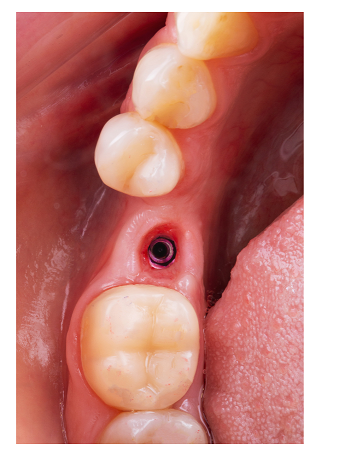

쉽게 설명해서 잇몸을 째지 않아도

수술이 가능합니다!

잇몸에 작은 구멍을 뚫어 심거나

발치와 동시에 진행하게 되면

잇몸을 절개하지 않아도 되는데요.

잇몸을 꿰매지도 않으니

붓기와 출혈도 적고

통증도 훨씬 덜합니다.